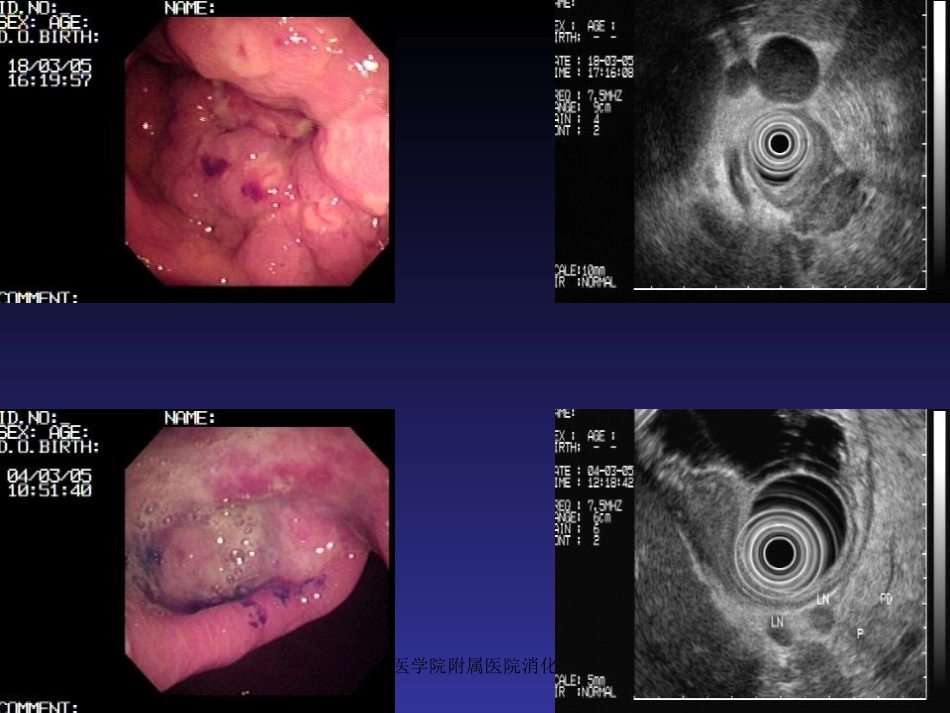

海南医学院附属医院消化内科•概述•胃、十二指肠出血分为:a)静脉曲张性出血b)非静脉曲张性出血消化性溃疡胃、十二指肠粘膜糜烂•非静脉曲肿瘤张性出血Dieculafoy氏溃疡血管畸形海南医学院附属医院消化内科海南医学院附属医院消化内科海南医学院附属医院消化内科海南医学院附属医院消化内科一.胃、十二指肠出血治疗方法•药物治疗•外科手术治疗•X线介入血管栓塞治疗•内镜下治疗内镜治疗优势:能够直观观察到胃、十二指肠出血部位,并能采取各种止血方法作相应止血治疗,从而避免以往常规外科手术治疗方法。海南医学院附属医院消化内科二、适应症与禁忌症适应症:•消化性溃疡并出血•Dieculafoy氏溃疡出血•急性胃粘膜病变并出血•血管畸形并出血•肿瘤并出血•Mallory-Weiss综合征•其他原因所致胃、十二指肠...